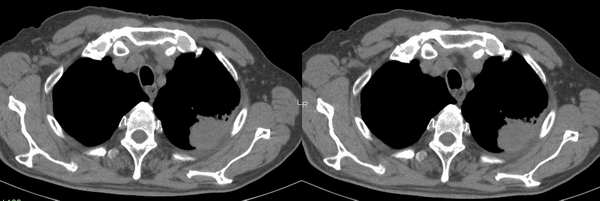

左肺上叶尖后段胸膜下软组织密度结节,形态不规则,可见浅分叶,短毛刺,与胸膜广基相连,夹角成锐角。复查10个月后明显增大。考虑周围型肺癌。

病灶较前增大,棘状突起/阻塞性肺炎并胸膜下线受侵,肋骨破坏-首先考虑肺癌。

支持周围型肺ca,理由:病变较上次明显增大;临近胸膜受侵犯;肋骨有破坏

补充昨日意见-考虑起源于胸膜可能性(恶性间皮瘤或转移瘤);因为近胸膜下小于1cm距离内周围型肺癌一般不引起胸膜增厚,复查见肿块增大,胸膜不均匀变厚,伴有肋骨破坏,图象不全,如有胸水,意义更大。